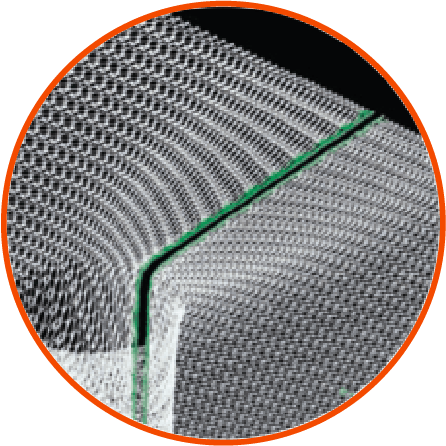

Dynamesh provides anatomically correct mesh for any mesh insertion, but due to its specialist features, the ISPT can be especially useful in the repair of parastomal hernias.

The ISPT implant is made from a single piece of mesh for a seamless junction with the elastic panel. The three-dimensional pre-shaped implant provides excellent elasticity and flexibility to facilitate improved stomaplasty preparation for surgeons.

The dual-layer composite structure promotes rapid ingrowth into the abdominal wall whilst reducing the risks of adhesions on the visceral side.

The elastic funnel is free of sharp selvedges, leading to secure integration of the terminal segment of the bowel and prevention of parastomal herniation.

The ISPT-R can be placed without detaching the stoma from the stoma wall, as the prefabricated slit makes it easier to place the mesh implant around the terminal section of the bowel.